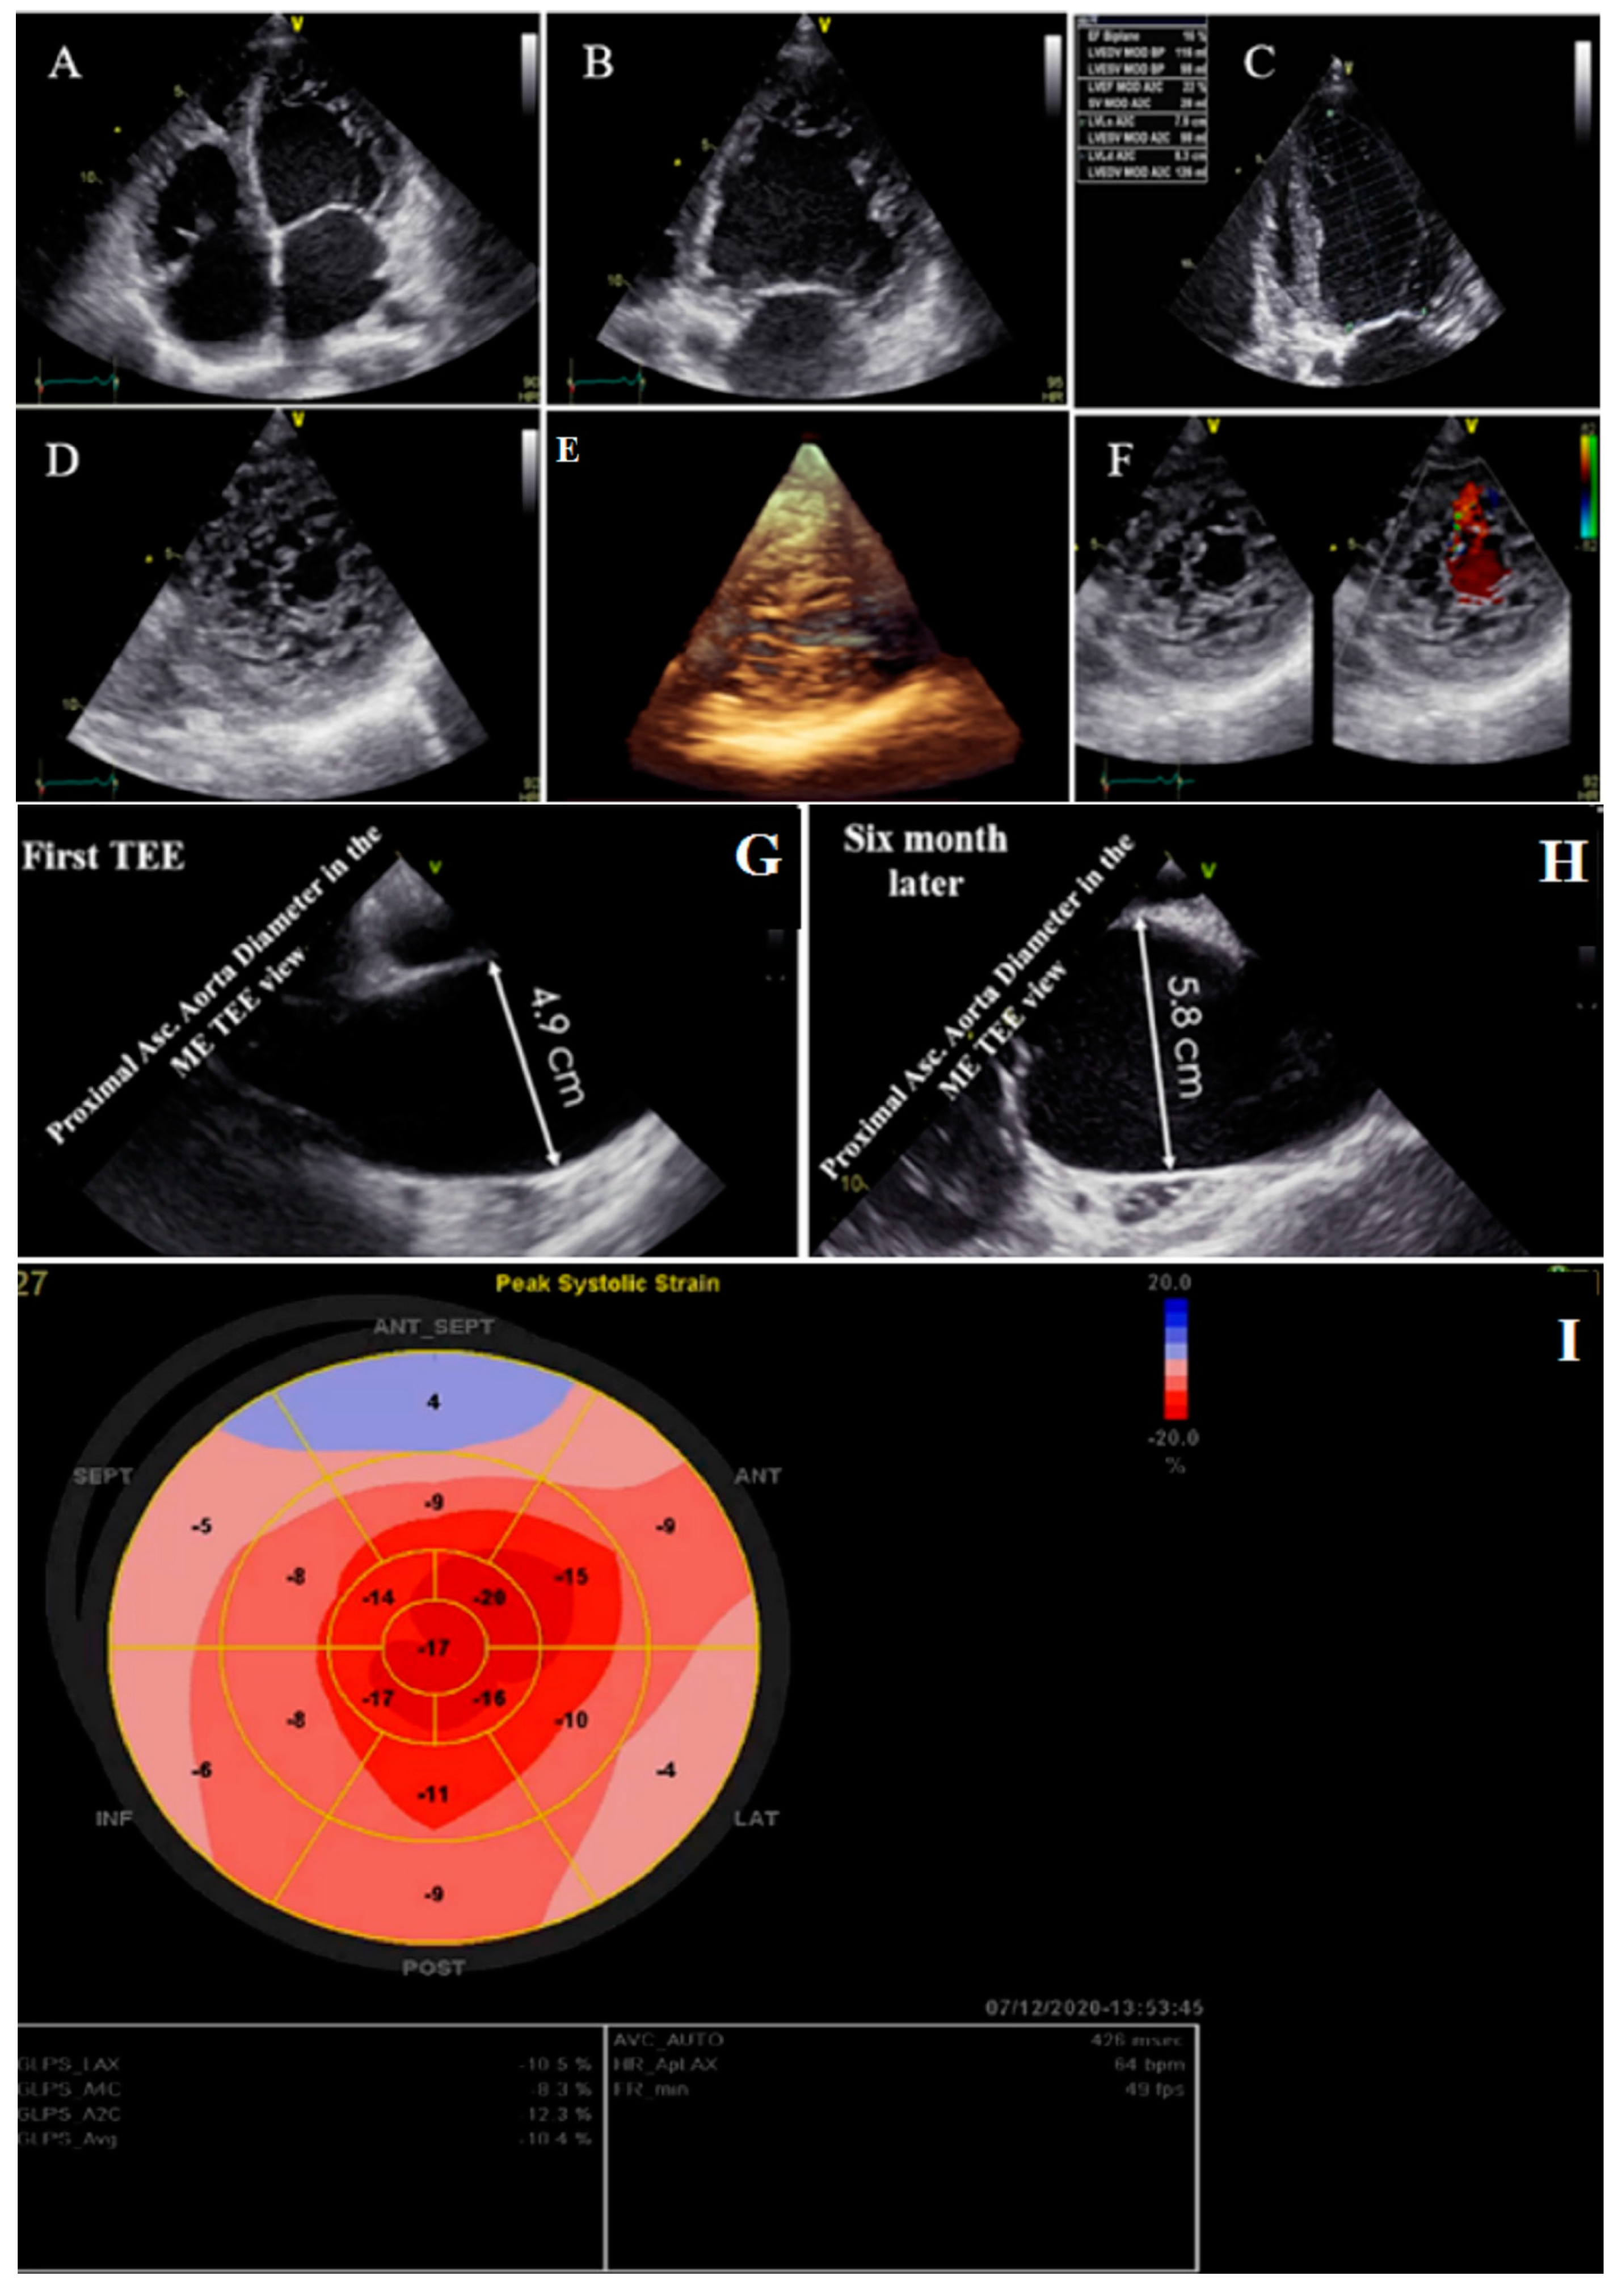

Figure 2.

Two- and three-dimensional transthoracic echocardiographic views of case #2: (A–C); left ventricular apical four and two-chamber views. (D,E); Apical SAX view, illustrating hypertrabeculated apical portions in addition to deep intertrabecular recesses and reduced left ventricular ejection fraction (LVEF = 16%, calculated by Simpson’s method). (F); Color Doppler echocardiography, showing evidence of direct blood flow from the ventricular cavity into deep intertrabecular recesses. (G,H); Transesophageal echocardiographic findings of baseline (left) and 6 months later (right); follow-up test showed fast-growing aortic root that reached 5.8 cm. (I); Speckle tracking echocardiographic findings, compatible with myocardial performance impairment plus relative apical sparing (GLS = −10.4%).